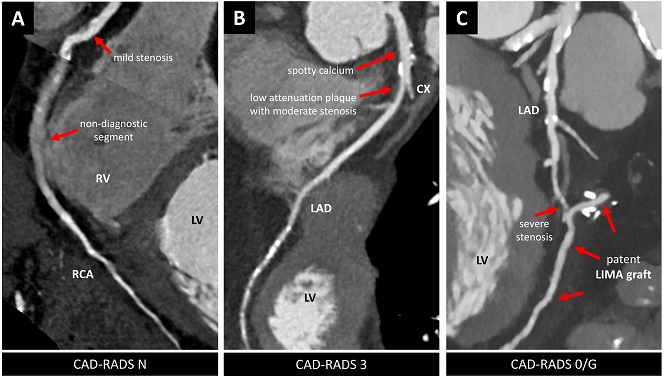

CAD-RADS is a tool for standardising coronary CTA reports.

CAD-RADS includes clinical treatment recommendations based on CTA findings.

Article: CAD-RADS – a new clinical decision support tool for coronary computed tomography angiography